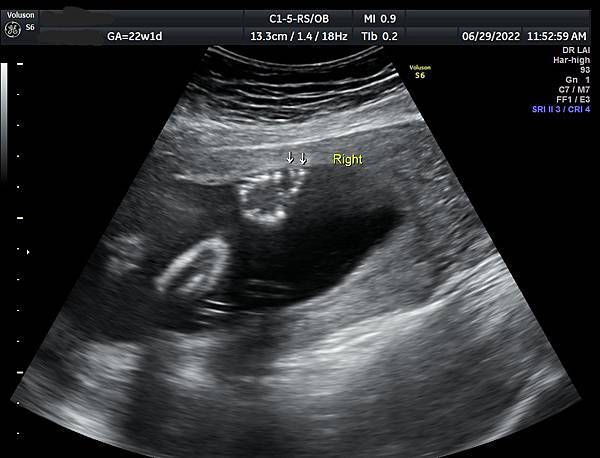

孕兒診所賴錫鉅醫師 377 產前診斷多指症經驗分享 : 多指症漏診是可能的,多比少好

產前診斷多指症經驗分享

多指症漏診是可能的,多比少好

產前診斷多指症 (1)